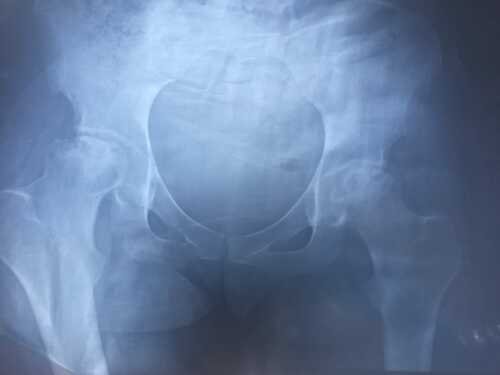

Estou com “Necrose Avascular Femoral Bilateral avançada", ou seja, a cabeça do meu fêmur tanto do lado direito, quanto do lado esquerdo, está rachando e se desfazendo, o que me impossibilita de fazer praticamente TUDO, inclusive andar ! Sentia dores desde Março de 2021, porém sem um diagnostico correto, continuei vivndo a base de remédios para melhorar, pois um ortopedista havia dito que era uma “ contratura muscular ”. O diagnóstico final foi dado em Março/22, onde precisei urgente fazer uso de muletas, para não jogar peso em cima da articulação do quadril e não piorar a situação, enquanto isso, exames e exames sendo realizados! Um dos médicos da rede pública disse que eu não poderia operar agora, por ser muito nova, porém, cheguei no estado que, não consigo simplesmente levantar e ir ao banheiro, e se levantar, não conseguir deitar novamente ! Já me encontrava desempregada quando começaram os sintomas, em março/21e portanto não possuo plano de saúde! Estive em consultórios públicos , paguei consultas particulares mesmo sem condições, e ainda assim recebi errados diagnósticos, o que atrasou meu resultado final de descobrir o que eu realmente tinha ! Eu evitei ao máximo de fazer essa vakinha, aguardando uma melhora ou resposta médica final, onde eu esperava ter outra saída, mas infelizmente não foi o que ocorreu. Outras formas de tratamento não são viáveis, por estar num nível avançado demais, então por insistência e conselhos de amigos e familiares, venho tentar alcançar o valor pesquisado para uma cirurgia bilateral +as taxas do site, e alguns exames e consultas! Lembrando que tenho pessoas pesquisando sobre hospitais e um processo em andamento para tentar operar o mais rápido possível. ATENÇÃO: Caso nesse tempo de arrecadação eu seja chamada , e faça uma das cirurgias, pelo sus, ou até mesmo as duas, o valor será doado a uma instituição (asilo ou orfanato), ou doado a outra pessoa que necessite em alguma outra vakinha ! "Mostrarei todo o processo em minhas redes" Sociais"